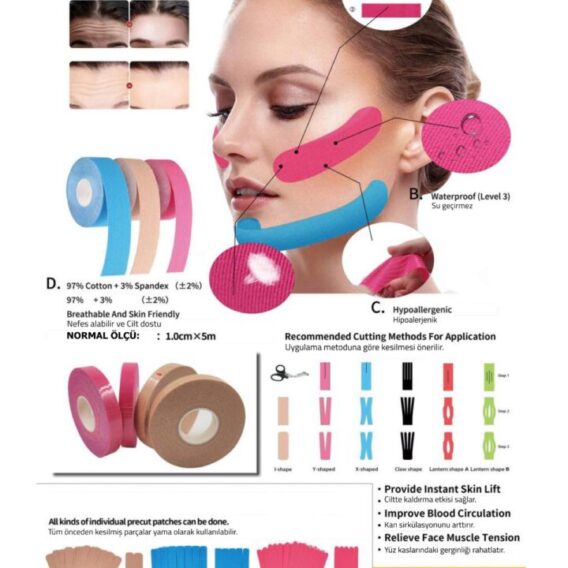

See all productsVaris Çorapları

See all productsEn Çok Satanlar